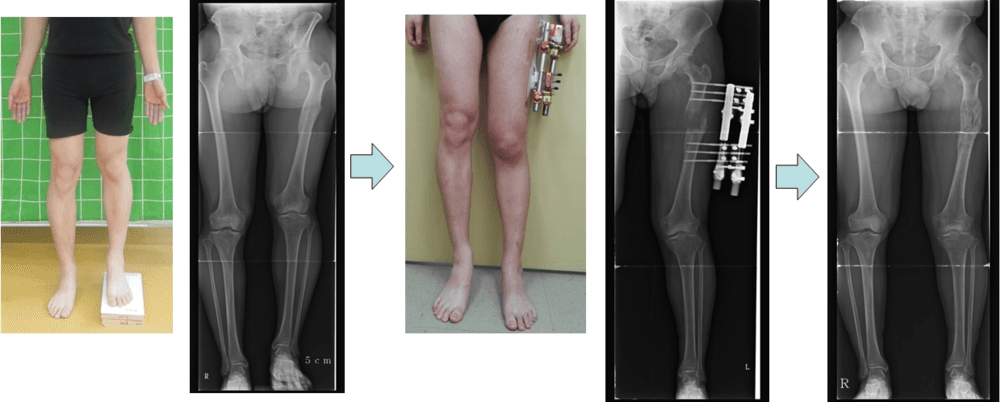

한쪽다리 짧은 환자에서 종아리뼈 연장